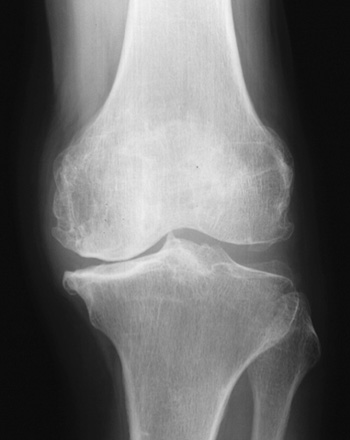

X線(レントゲン)による分類

下の写真は左膝関節のレントゲンです。骨の間にある隙間を関節裂隙(かんせつれつげき)と呼び、主に軟骨の厚みを示しています。病期が進行するにしたがって軟骨がすり減るため、関節裂隙が狭小、消失します。

正常

関節裂隙は保たれています

初期

関節裂隙の軽度狭小化

進行期

関節裂隙の狭小化

骨棘(骨のトゲ)の形成

末期

関節裂隙の消失